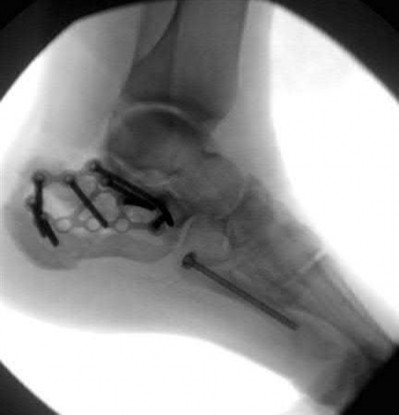

Figure A shows an unstable bilateral pelvic ring injury. Percutaneous posterior iliosacral screw fixation places the L5 nerve root at risk as it courses across the sacral ala. Injury to the L5 nerve root would typically result in weakness in great toe extension and sensory changes on the dorsum of the foot. It is important to notice that L5 often partially innervates tibialis anterior along with L4, so weakness to ankle dorsiflexion may be present as well. Illustration A shows the post-operative films with bilateral iliosacral screws.